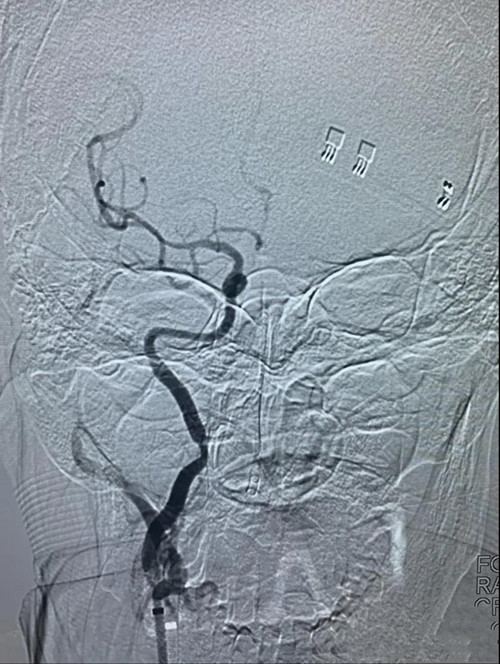

经取栓治疗后,原本闭塞不通的右颈内动脉-右大脑中动脉变得通畅无阻,但右颈内动脉闭塞处经球囊扩张成型后仍存在严重的“一线天”重度狭窄,随时可能在发生闭塞,与家属沟通后,决定为患者进行右颈内动脉支架植入彻底治疗病变。

右颈内动脉支架定位后释放支架,血管成型良好。

正侧位造影显示右颈内动脉-右大脑中动脉开通良好,血流恢复正常。